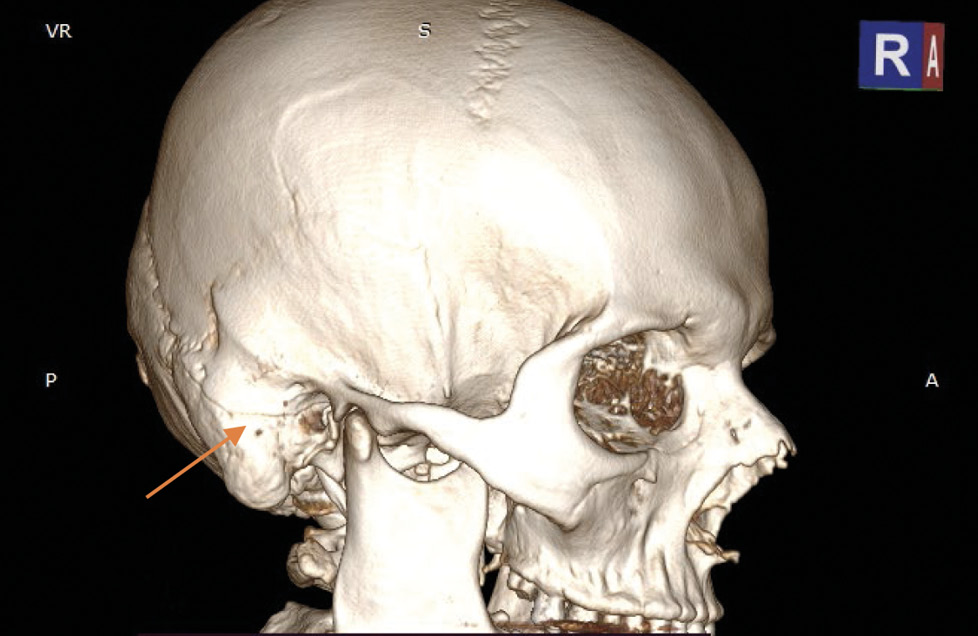

На экспертизу дополнительно представлены результаты мультиспиральной компьютерной томографии головного мозга гражданина Л., благодаря которым экспертом выявлено следующее. На серии компьютерных томограмм (с последующим 3D-моделированием) в лобно-височно-теменной области слева субдуральная гематома максимальной толщиной до 4 мм. В полюсно-базальных отделах левой височной доли определяются мелкие очаги геморрагической плотности, местами сливного характера (рис. 1, 2). Боковые желудочки симметричные. Срединные структуры мозга не смещены. Субарахноидальное пространство нивелировано слева. В бороздах мозга левой височной, левой теменной долей геморрагическое содержимое (субарахноидальное кровоизлияние), малая эпидуральная гематома правой теменно-височной области. Перелом сосцевидного отростка правой височной кости: линия перелома распространяется на пирамиду правой височной кости и заднюю стенку наружного слухового прохода (рис. 3–5). Наличие геморрагического содержимого в ячейках правого сосцевидного отростка, в антруме справа и в правой барабанной полости.

Рис. 5. Мультиспиральная компьютерная томография головного мозга: перелом сосцевидного отростка правой височной кости с переходом на заднюю стенку наружного слухового прохода (стрелка) на 3D-модели.